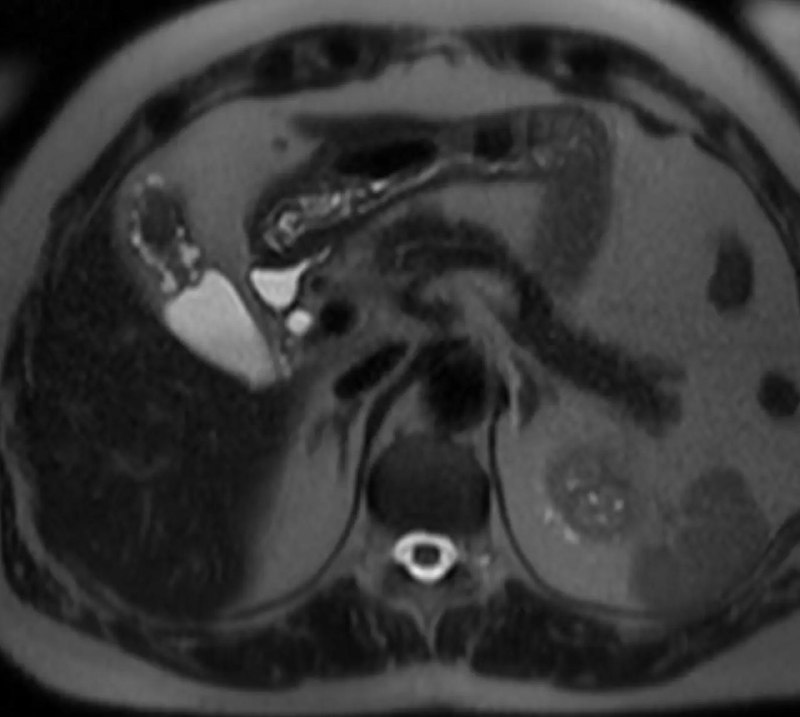

Аденомиоматоз (расширение синусов Ашоффа-Рокитанского, которые представляют собой выпячивания или дивертикулыслизистой оболочки желчного пузыря, расположенные в мышечном слое) желчного пузыря во фригийском колпаке (распространенная, не имеющая клинического значения анатомическая особенность, при которой дно желчного пузыря прилегает к его телу, напоминая мягкий остроконечный колпак средневековья. Обнаруживается при визуализации (УЗИ, КТ, МРТ), не вызывает симптомов и не требует лечения и наблюдения. Впрочем, как и сам аденомиоматоз.